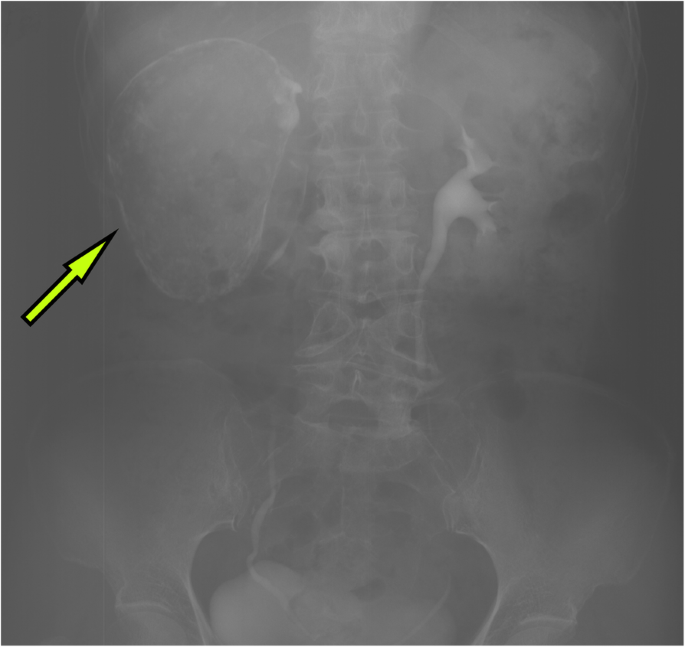

A 63-year-old woman was admitted to the hospital with intermittent right lumbar pain, without other symptoms such as fever, weakness, weight loss, and other joint-related symptoms (swelling, joint stiffness, etc.). The patient had a history of right lumbar trauma 2 years prior and hypertension and multiple lacunar infarcts for 6 months. The patient was treated with rosuvastatin calcium (5 mg once daily), compound Danshen tablets (0.96 g once daily), and benazepril hydrochloride (2.5 mg once daily). The patient denied a history of tuberculosis and a related family or consanguinity history of tumoural calcification. Clinical examination revealed no swelling, tenderness and percussive pain in the right lumbar region and no nodules or masses on each joint. Serum phosphate, total calcium, ionized calcium, urea, creatinine, alkaline phosphatase, arterial blood gas analysis, albumin, and uric acid levels were within the normal range (Table 1), and the tuberculin or purified protein derivative (PPD) test result was negative. Computed tomography (CT) scanning and spiral CT 3-D imaging revealed a large cystic lesion on the lateral side of the right kidney, with the circular calcified wall around the lesion, which compressed, deformed and displaced the right kidney. In the annular calcified wall, a low-density circular mass with a size of 11.5 × 6.9 × 5.1 cm and a CT value of 15 HU were identified (Figs. 1 and 2). The density of the circular lesion did not increase in the enhanced CT scan (Fig. 3). Plain X-ray film of the kidneys, ureters and bladder (KUB) showed a high-density shadow in the right waist area measuring 10.2 × 7.5 cm (Fig. 4). In addition, intravenous urography (IVU) revealed that the size of the right kidney decreased, a large cystic lesion was found on the lateral side of the right kidney, and only a few minor calyces were found (Fig. 5).